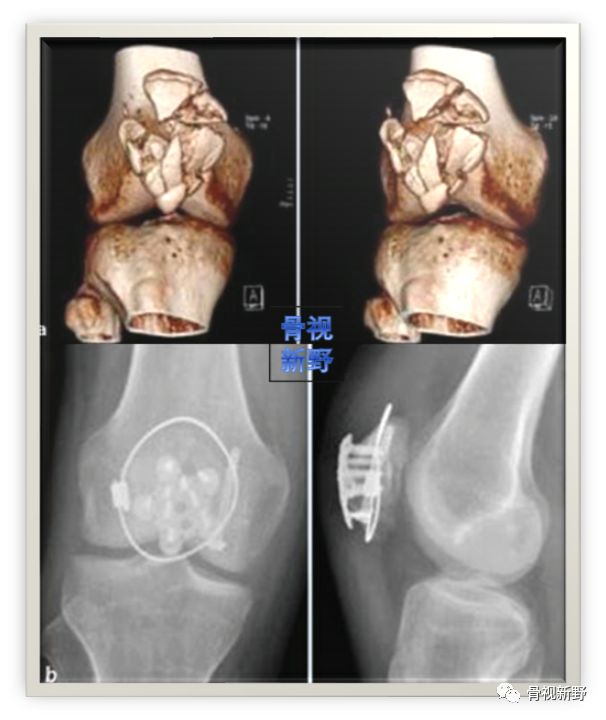

篮状钢板+编织缝合

最早在2006年,Matejcic等用篮状钢板进行髌骨粉碎骨折的固定,获得良好效果。

篮状钢板(basket plate),1988年由Branimir Smiljanic 医生设计,主要用于髌骨下极的粉碎骨折。

篮状钢板有利于收集粉碎骨折块、特别是下极粉碎骨折。该钢板有四个钉孔,半螺纹松钉打入对侧骨块以获得骨碎块间的加压。

术中所见

X光所见